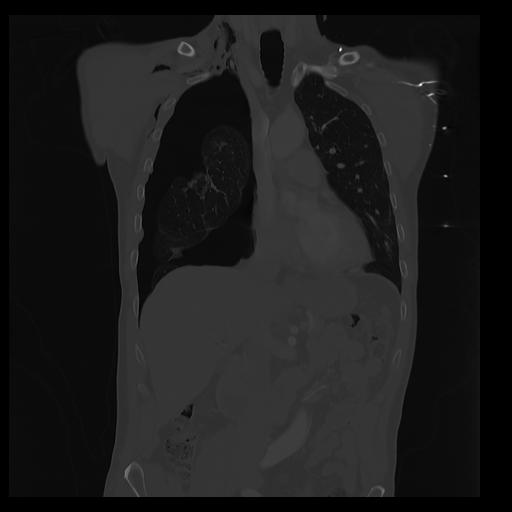

32 PULMON,CE,Coronal,3.000,PULMON,Coronal,